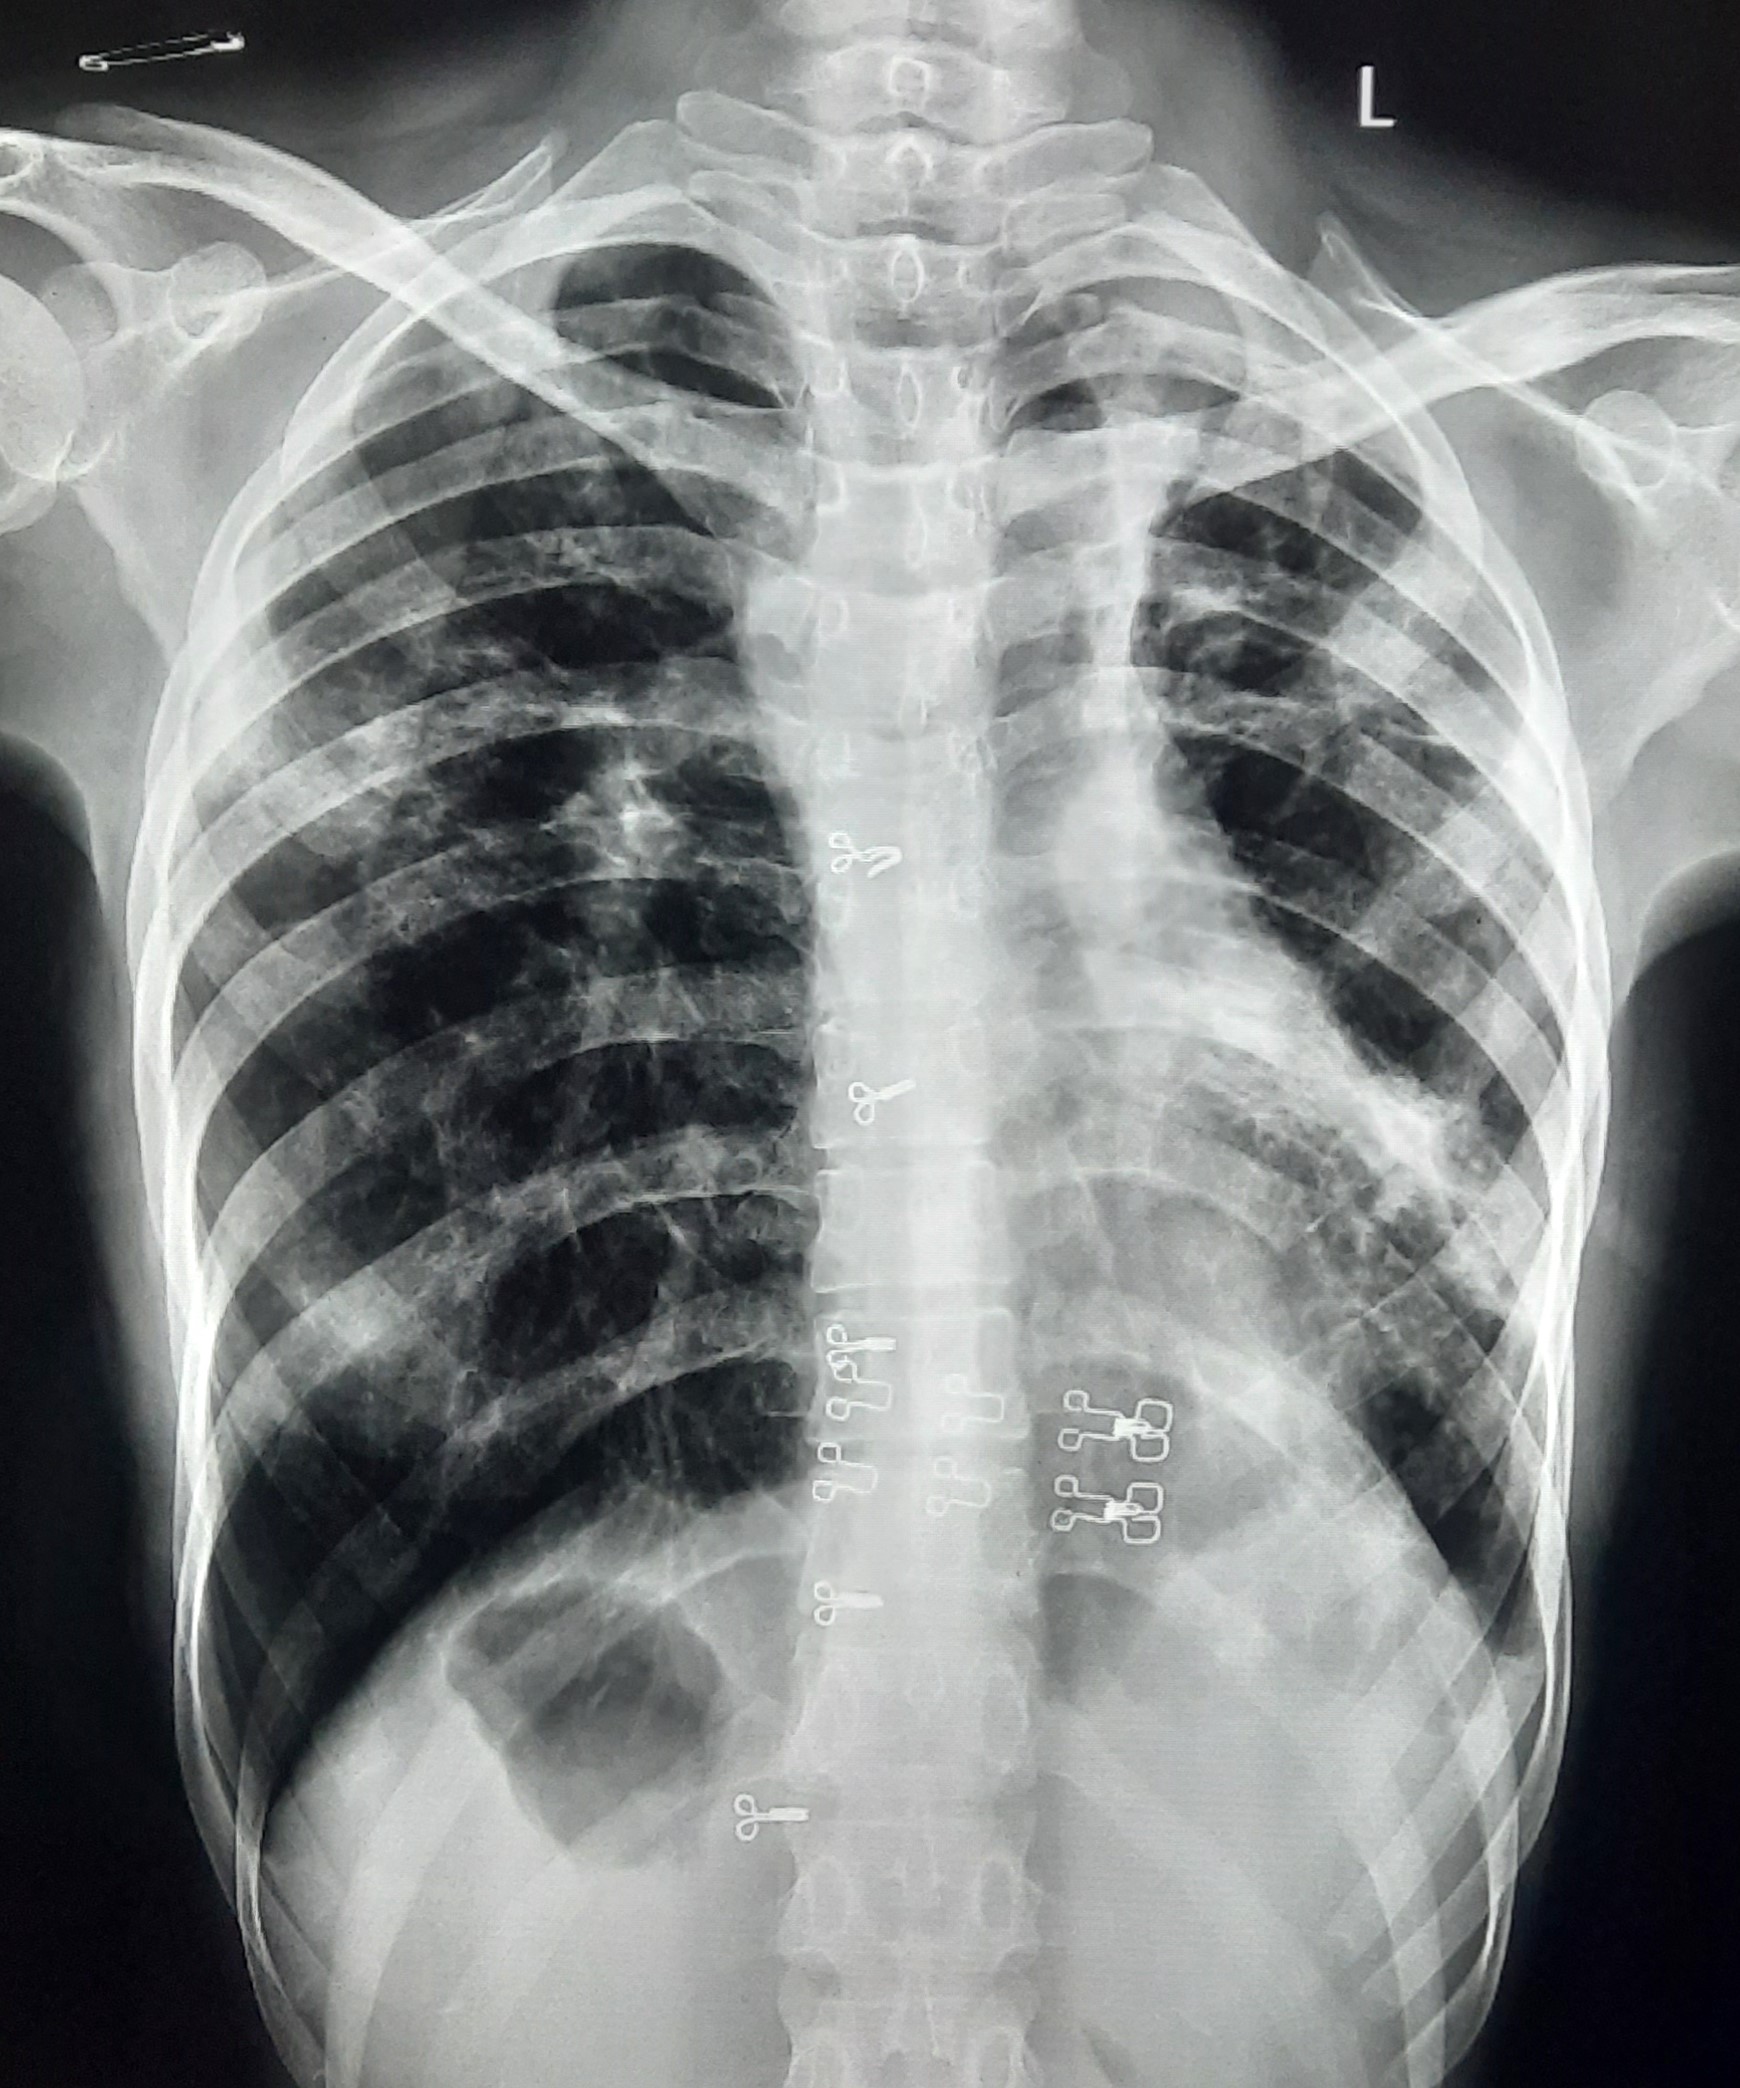

| 53 | IGGMC, Nagpur, Nagpur | P2 | 29-4419 | Rasul Ali | Consent taken on Paper | 36 Yrs. |

Provisional Diag : ?

Final Diag : COPD |

Non-TB Case (Confirmed) | Prominence of broncho vascular markings in bilateral Mid zone il Defined Non-Homogenous Lesion, Changes Of COPD | Abnormality visible on x-ray |